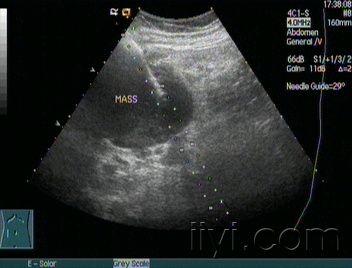

腹腔非何杰金氏淋巴瘤声像图 - 超声医学讨论版 - 医